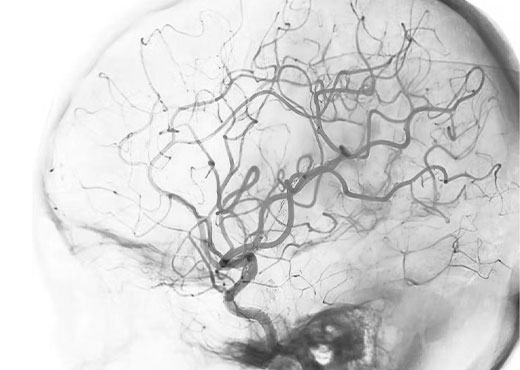

EN EL CEREBRO

A través de estos procedimientos tratamos enfermedades de las arterias del cerebro, tales como: aneurismas cerebrales y malformaciones arteriovenosas (MAV’s).